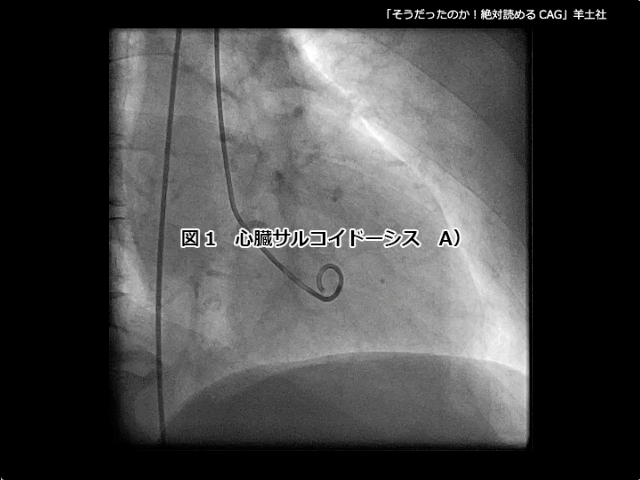

そうだったのか! 絶対読めるCAG【付録動画サンプル】